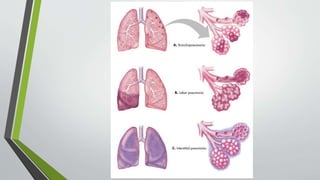

PATHOPHYSIOLOGY

Causative organism

Inflammatory reaction in alveoli

Formation of exudates(RBCs, fibrin and poly morpho nuclear leukocytes

infiltrate the alveoli)

Containment of virus in alveoli causes consolidation of leucocytes/fibrin within

the affected area

Stage of congestion( engorgement of alveolar spaces with fluid and hemorrhagic

exudates which causes spread of pathogens through the lobe)

Stage of red hepatization(coagulation of the red exudates occurs and the affected

lung appears red)

Stage of grey hepatization( the decrease in RBC count is replaced by neutrophils

which infiltrates the alveoli making the lung tissue solid and greyish in color)

pneumonia

PATHOPHYSIOLOGY Causative organism Inflammatory reactionin alveoli Formation of exudates(RBCs, fibrin and poly morpho nuclear leukocytes infiltrate the alveoli) Containment of virus in alveoli causes consolidation of leucocytes/fibrin within the affected area

. Stage of congestion(engorgement of alveolar spaces with fluid and hemorrhagic exudates which causes spread of pathogens through the lobe) Stage of red hepatization(coagulation of the red exudates occurs and the affected lung appears red) Stage of grey hepatization( the decrease in RBC count is replaced by neutrophils which infiltrates the alveoli making the lung tissue solid and greyish in color) pneumonia